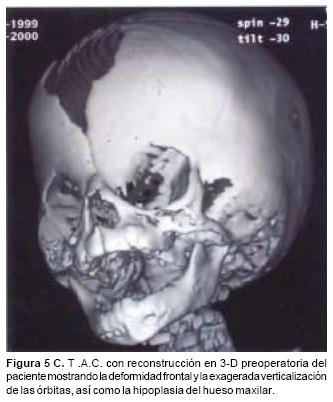

Las osteotomías a utilizar se diseñan previamente en las reconstrucciones tridimensionales obtenidas con la T.A.C., y ésta varía de acuerdo a la deformidad de cada paciente. Las más utilizadas son: osteotomías fronto–orbitarias bilaterales (Figura 1), osteotomía tipo monobloque (Figura 2) y osteotomía fronto–orbito–malar unilateral (Figura 3). La osteotomía seleccionada se dibuja sobre la estructura esquelética disecada utilizando violeta de genciana. En este momento se selecciona 2 o 3 sitios sobre el hueso frontal para las craneotomías. Y una vez completadas estás, se realiza una disección intracraneana muy limitada que sigue las líneas de las osteotomías en el área frontal y orbitaria, creando una serie de túneles intracraneanos y preservando la mayoría de los puentes vasculares entre las meninges y el hueso frontal. El mismo procedimiento se utiliza para el techo orbitario. A través de los túneles se introducen tiras de gasas y separadores muy finos que permiten la realización de las osteotomías con sierras oscilatorias, sin daño a las estructuras subyacentes. Con un endoscopio rígido de visión directa se verifica la hemostasia y la integridad de las meninges luego de realizar las osteotomías. Así mismo bajo visión endoscópica se realiza una cuidadosa disección del área de la Crista Galli y de las alas menores del esfenoides en su unión con la órbita y el frontal, lo que permite completar las osteotomías a nivel central y lateral y la movilización de toda la estructura ósea a avanzar. En los casos de monobloque, la línea de osteotomía se continúa de la pared lateral orbitaria a la unión pterigomaxilar y sobre el piso y la pared medial de la órbita. En estos casos la disyunción con pinzas de Rowe del área pterigomaxilar, se hace necesario a fin de avanzar en un verdadero monobloque el maxilar unido a las órbitas y al hueso frontal (Figura 2).

En todos los pacientes se logró el avance planificado de los segmentos óseos, al corregir la deformidad del hueso frontal, el exorbitismo y en la retrusión del tercio medio en los casos con avance en monobloque. Los avances mayores se obtuvieron en el hueso frontal y variaron entre 16 y 30 mm., mientras que los menores fueron los del hueso maxilar que fluctuaron entre 9 y 16 mm. (Cuadro I). Radiológicamente los controles postoperatorios tempranos mostraron inicialmente áreas de hipodensidad ósea, que al final del periodo de consolidación cambiaron a áreas de densidad ósea radiológica normal, lo que significa neoformación de hueso. Las áreas de hueso neoformadas que consolidaron en forma más rápida, son las ubicadas en las líneas de osteotomía de la unión pterigomaxilar, pared lateral de la órbita y unión frontoorbitaria. Las áreas que más tardaron en consolidar incluye la porción lateral y superior del hueso frontal.

También los controles radiológicos durante el proceso de distracción mostraron que no se produjo la creación de espacios muertos intracraneanos durante los avances. En todos los pacientes con sinostosis bicoronal el avance frontoorbitario produjo excelentes resultados estéticos dando una nueva forma a la región frontal y proyectando mejor el reborde supraorbitario. En los niños con enfermedad de Crouzon y síndrome de Apert, se corrigió en forma muy satisfactoria el exorbitismo al resolver las graves exposiciones corneales (Figuras 5 A, B, C, D, E, F, G, H), en los que se utilizó el avance simultáneo del tercio medio, este cambio óseo corrigió muy satisfactoriamente la retrusión del mismo, ampliando la vía aérea y resolviendo en muchos casos grandes problemas ventilatorios durante el sueño (Figuras 6 A, B, C, D, E, F). Los pacientes con plagiocefalia corrigieron significativamente la deformidad frontoorbitaria y los tejidos blandos suprayacentes se adaptaron a la nueva estructura ósea. La clásica órbita de arlequín de estos niños producida por la sinostosis del frontal con el esfenoides, inmediatamente se ve corregida en su forma y su configuración se hace muy similar con la órbita contralateral (Figura 7)(Fig. 7a, 7b, 7c, 7d, 7e, 7f, 7g) (Cuadro II).